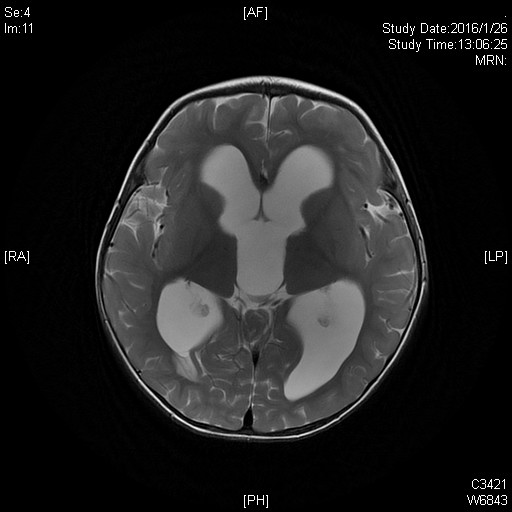

髓母细胞瘤是颅内恶性程度最高的胶质瘤,生长迅速,手术不易全部切除。经过神经外科科内讨论,为小萌制定了详细的手术方案,行肿瘤切除术。麻醉科也给予小萌特别的关爱,在手术室,麻醉科张欢主任和主治医师魏昌伟上下同时开工,一位动脉穿刺,一位股静脉植管。麻醉过程紧张有序,有条不紊。主刀医生王贵怀主任擅长高位颈髓和脑干肿瘤手术,处理四脑室肿瘤游刃有余。手术中肿瘤暴露、分离、切除、止血,步步为营,干净利落。手术很成功,肿瘤全切,约5.0mm×3.5mm,足有鸡蛋大小。术后小萌入ICU,在ICU的精心治疗下,他恢复很快,术后第2天返回普通病房治疗。术后住院日,小萌病情平稳,恢复良好,于2016年2月19日出院。术后病理证实小萌脑部肿瘤为髓母细胞瘤。